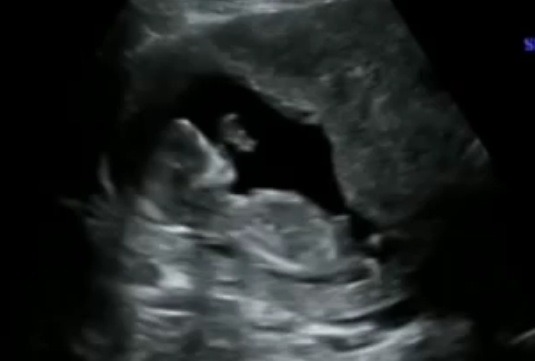

It was hard to see a nub because everything was fast moving. I tried to slow it down and saved some stills for you- but not sure any of them show a nub (maybe the first?).....

Attachment 6621